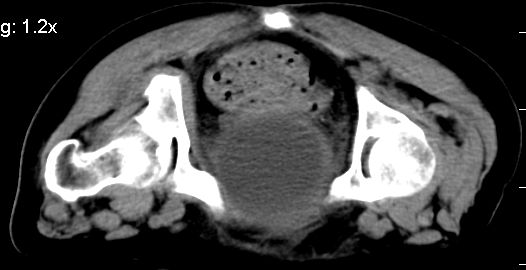

膀胱充盈可,壁光滑厚薄尚均匀,其内下方可见不规则的致密影,建议做膀胱镜检查

膀胱癌突破浆膜可能性大

考虑膀胱癌可能性大伴双侧输尿管下端扩张.

膀胱后壁见不规则致密影,我们遇到这样的病人都再做一次俯卧位扫描;排出膀胱内凝血块。

1.膀胱后壁见不规则致密影,占位?膀胱内凝血块?建议俯卧位扫描、膀胱镜检查.

2.双侧输尿管下段扩张.

膀胱三角区不规整软组织改变,双侧输尿管扩张,所以占位性病变肯定首先考虑,建议改变体位扫描除外游离血块影,但老年人出血原因一定要查明。